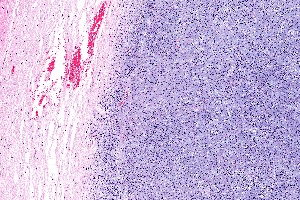

Até o momento, o diagnóstico dessas doenças é feito por patologistas em análises de tecidos dos tumores em microscópio. Agora, com a “análise molecular e integração com os dados clínicos, nós podemos auxiliar os clínicos a reclassificar os indivíduos com câncer cerebral, que pode levar ao melhor diagnóstico e abrir novas oportunidades para melhorar os protocolos de tratamento”, afirma o Dr. Houtan.

Ainda, segundo o pesquisador, esses dados moleculares ajudam os médicos a distinguir o caso específico de seu paciente e indicar uma forma mais específica de tratamento ou então evitar terapias desnecessárias. “Nossa expectativa é que as mutações somáticas identificadas possam complementar o diagnóstico tradicional baseado apenas em critérios histopatológicos, levando a um diagnóstico e tratamento mais precisos”, revela.